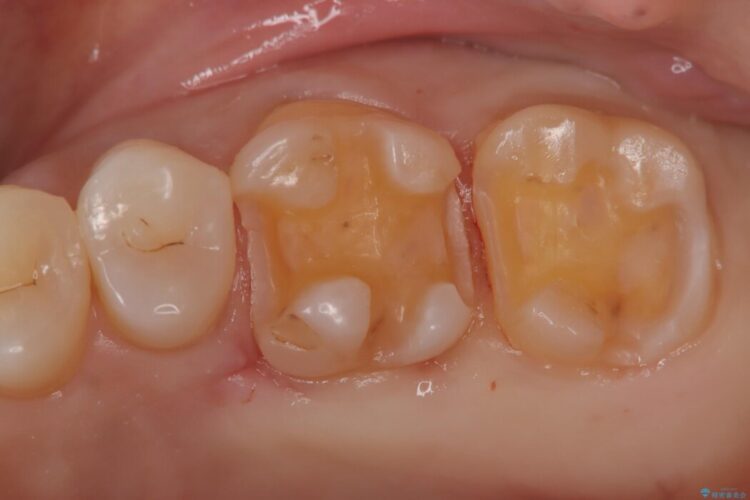

今ある金属の詰め物をメタルフリーのものにやりかえたいとの主訴で来院されました。

金属の詰め物を除去して虫歯の処置をした後にセラミックインレーにて修復しました。